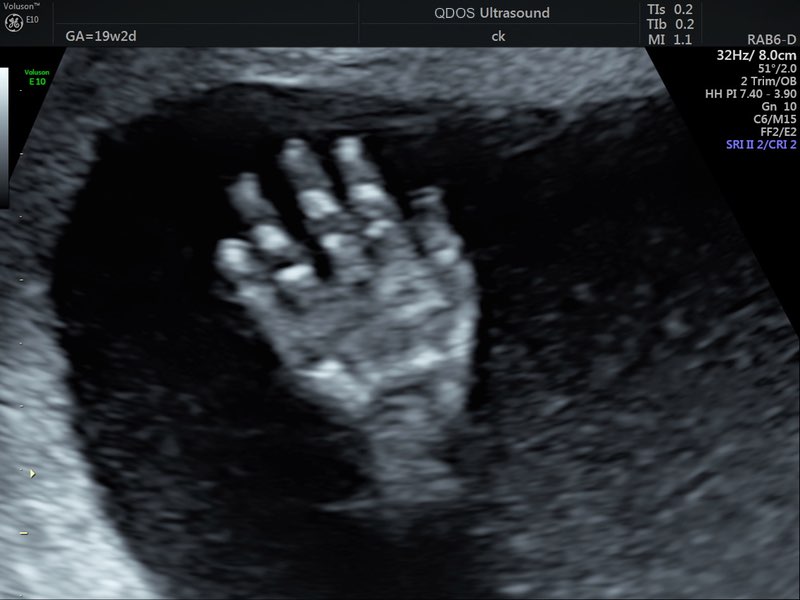

The Anatomy scan is a key milestone in your pregnancy and offers the most detailed check of your baby’s development. At this stage, your baby is large enough for a thorough examination and developed enough to show clear signs of growth and movement, providing valuable insights. The scan is also clear enough to capture detailed images, as your baby’s bones (which can block the ultrasound waves and therefore the picture) haven’t fully developed yet.

Generally performed between 19-21 week gestation, the scan ensures a comprehensive review of your baby’s development, including the skull, brain, face, chest, heart, stomach, kidneys, spine, limbs, and more. If you’d like, we can usually determine the baby’s sex at this stage. Additionally, we’ll check the amniotic fluid level and overall fetal proportions.